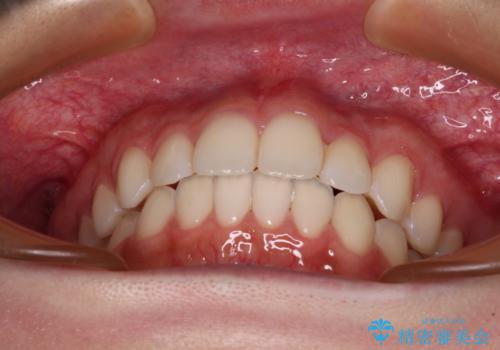

インビザライン特有の、奥歯の咬み合わせの問題もなく、しっかりと歯列を改善することができました。

舌側転位している上顎側切歯(内側に引っ込んでいる真ん中から2番目の歯)は、インビザラインが最も移動を苦手とする歯であり、これ以上の改善を望まれる場合にはワイヤー矯正、あるいはワイヤー矯正の併用をお勧めいたします。